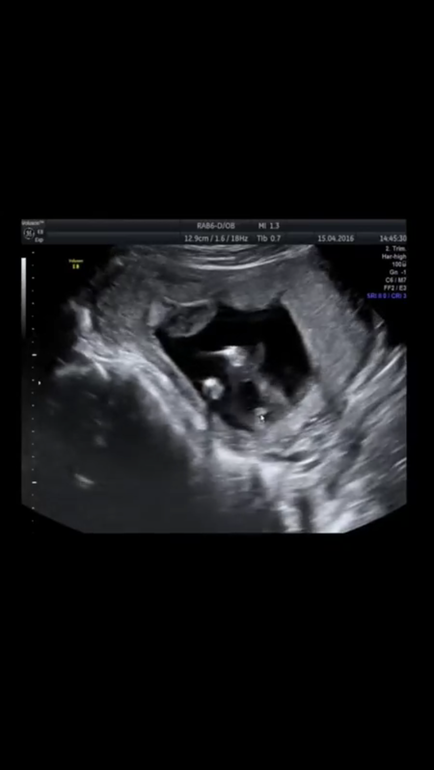

Вот если поймёте.15,4 недель.попой к экрану,две ноги наверх,между ними валик и никакой пипирочки) но мне и в 13 сразу сказали что девочка,и в прошлый раз и сейчас

17.07.2016

А у нас диск дают,там полностью запись идёт всего) я вот скриншот сделала) у мальчишки бы там ещё гвоздик торчал